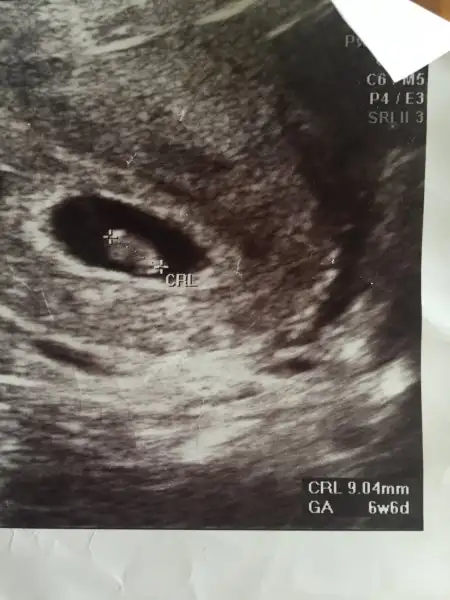

Acaba Ramzi teorisi ve genital nub çıkıntısına göre söyleyebilir misiniz hanımlar

Eklentiler

• IMG_0107.webp

IMG_0107.webp

7,3 KB · Görüntüleme: 125